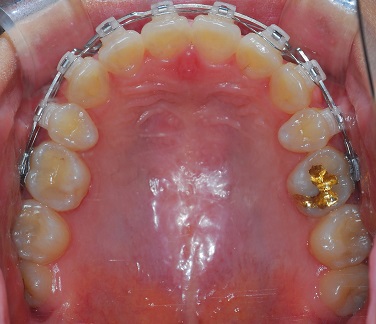

상악 사진